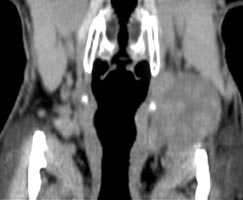

При компьютерной томографии было подтверждено наличие объемного образования с участками повышенной (54 ед.) и пониженной (30 ед.) плотности (рис. 2). Образование раздвигает окружающие ткани и оттесняет левую подчелюстную слюнную железу кпереди.

Рис. 2. Компьютерная томография мягких тканей шеи